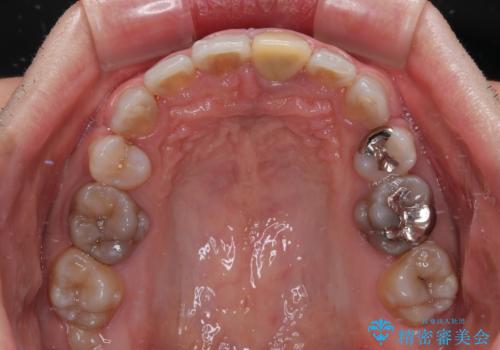

口元を引っ込めるために上下左右の第一小臼歯4本を抜歯することとしました。

特徴的な歯の色が気になっているとのことで、今後セラミッククラウンによる審美歯科治療を検討されているとのことで、矯正治療の後戻りが落ち着いたタイミングで治療を進めていく予定です。